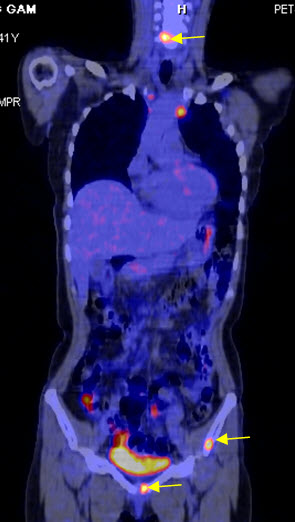

Hình 4 (a, b) cho thấy giá trị của PET/CT trong đánh giá giai đoạn của ung thư vú. Bệnh nhân Nguyễn Th. T. Tr., nữ, 63 tuổi, chẩn đoán là ung thư vú. Kết quả PET/CT toàn thân cho thấy nhiều tổn thương di căn hạch cổ, hạch trung thất, di căn 2 phổi, gan, xương tăng hấp thu FDG.

Hình 4a. Hình PET toàn thân thấy nhiều tổn thương hạch cổ, hạch trung thất (mũi tên vàng), phổi (mũi tên đỏ), gan (mũi tên tím) và xương (mũi tên xanh) tăng hấp thu FDG.

Hình 4b. Hình PET/CT ở mặt phẳng cắt ngang thấy tổn thương di căn phổi (mũi tên đỏ) và di căn gan (mũi tên da cam).